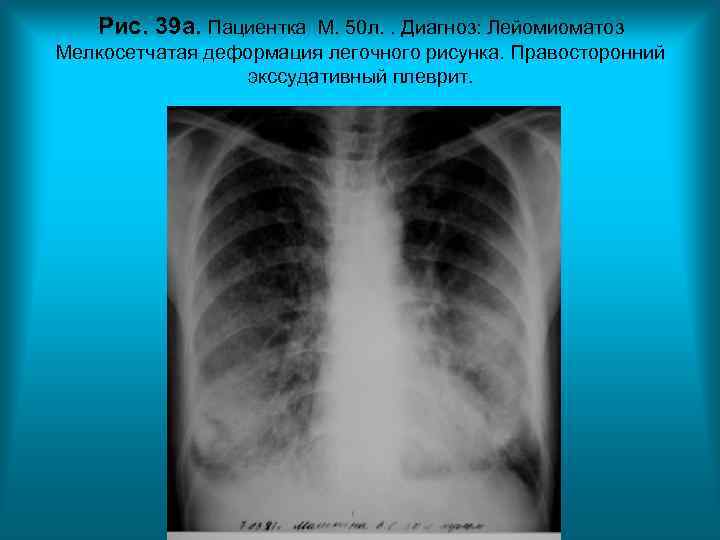

Рис. 39 а. Пациентка М. 50 л. . Диагноз: Лейомиоматоз Мелкосетчатая деформация легочного рисунка. Правосторонний экссудативный плеврит. Н. С. Воротынцева. С. С. Гольев Рентгенопульмонология

Рис. 39 б. Пациентка М. 50 л. Диагноз: Лейомиоматоз Мелкосетчатая деформация легочного рисунка. Правосторонний экссудативный плеврит.